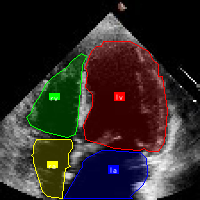

本数据集名为'sono-v1',于2024年12月3日创建,采用CC BY 4.0许可证授权,由qunshankj平台用户提供。该数据集专门用于超声心动图中心腔结构的计算机视觉研究,包含102张经过预处理的心脏超声图像。所有图像均已调整为640×640像素的统一尺寸,采用拉伸方式处理以保持原始内容。数据集采用YOLOv8格式进行标注,主要针对心腔中的四个关键结构:左心房(la)、左心室(lv)、右心房(ra)和右心室(rv)。数据集已按照标准划分为训练集、验证集和测试集,为模型的训练、评估和测试提供了完整的数据支持。该数据集的创建目的是支持基于深度学习的超声心动图自动分析系统,特别是心腔结构的自动检测与定位,有助于提高心脏疾病诊断的效率和准确性。